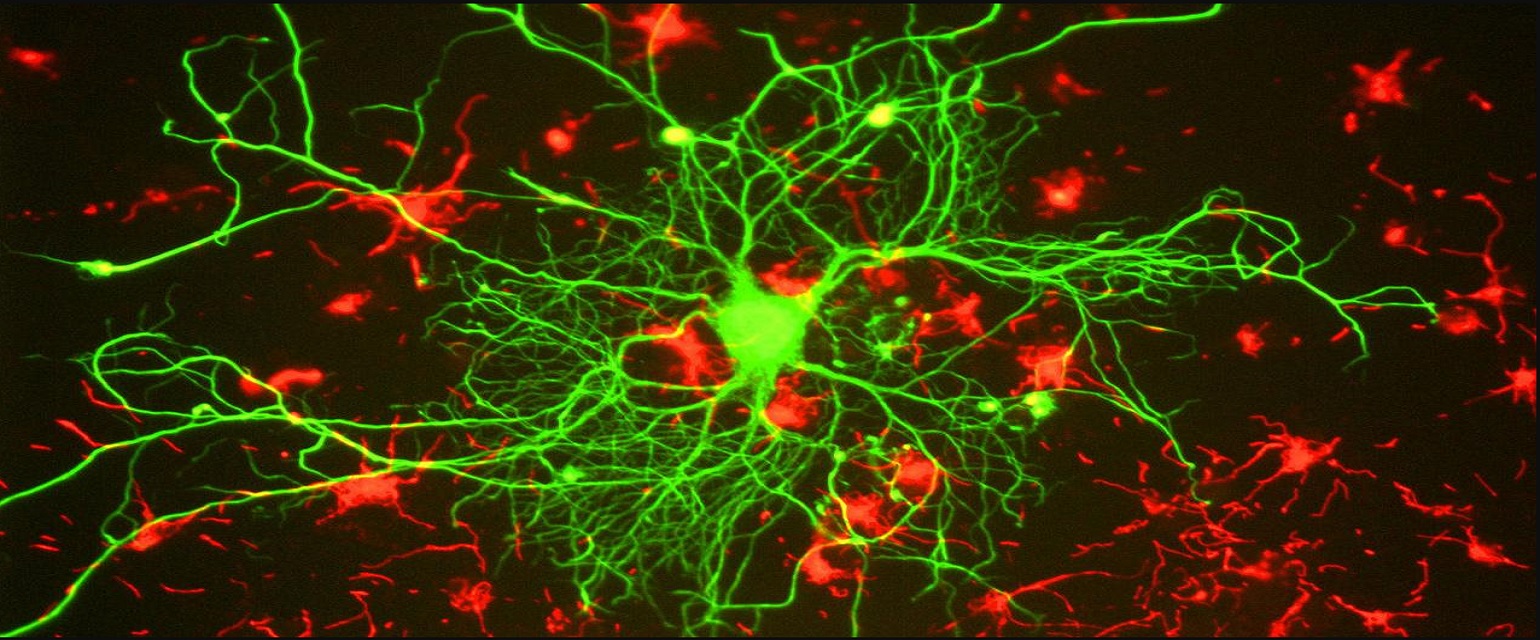

Lo que sí se ha demostrado es que la alimentación tiene un papel importante en la prevención de la enfermedad y para frenar su avance. El motivo está en la propia naturaleza de la enfermedad. Tal y como explica el nutricionista Aitor Sánchez García en su blog Mi Dieta Cojea, el deterioro de las funciones cerebrales está causado por la pérdida de la sinapsis neuronal, que es la conexión y envío de información de unas neuronas a otras. Esa sinapsis se produce gracias a las membranas neuronales, formadas por unos componentes llamado fosfolípidos.